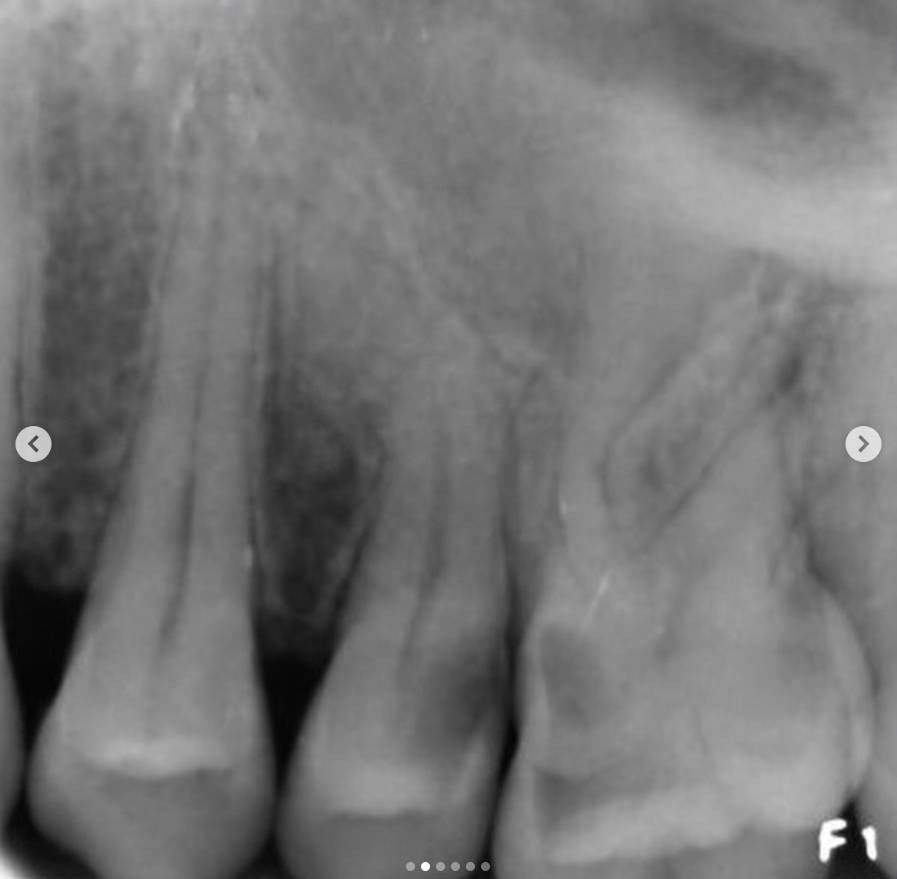

• The roots exhibit two curvatures, and although there are two canals, they converge at a single apical foramen.

4. A working length radiograph was taken with gutta-percha cones to confirm canal length.